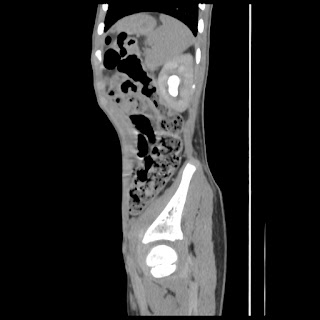

A 07 years old child with left side of abdomen pain

current CT images: